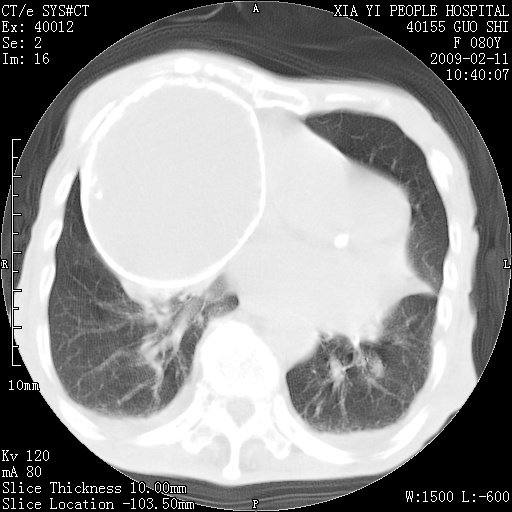

以下是引用随光逐影在2009-2-16 16:34:00的发言:[br]1)考虑右前纵隔皮样囊肿。2)双侧少量胸腔积液。

以下是引用zjzjr在2009-2-16 17:30:00的发言:[br]支持囊性畸胎瘤 双侧少量胸腔积液。